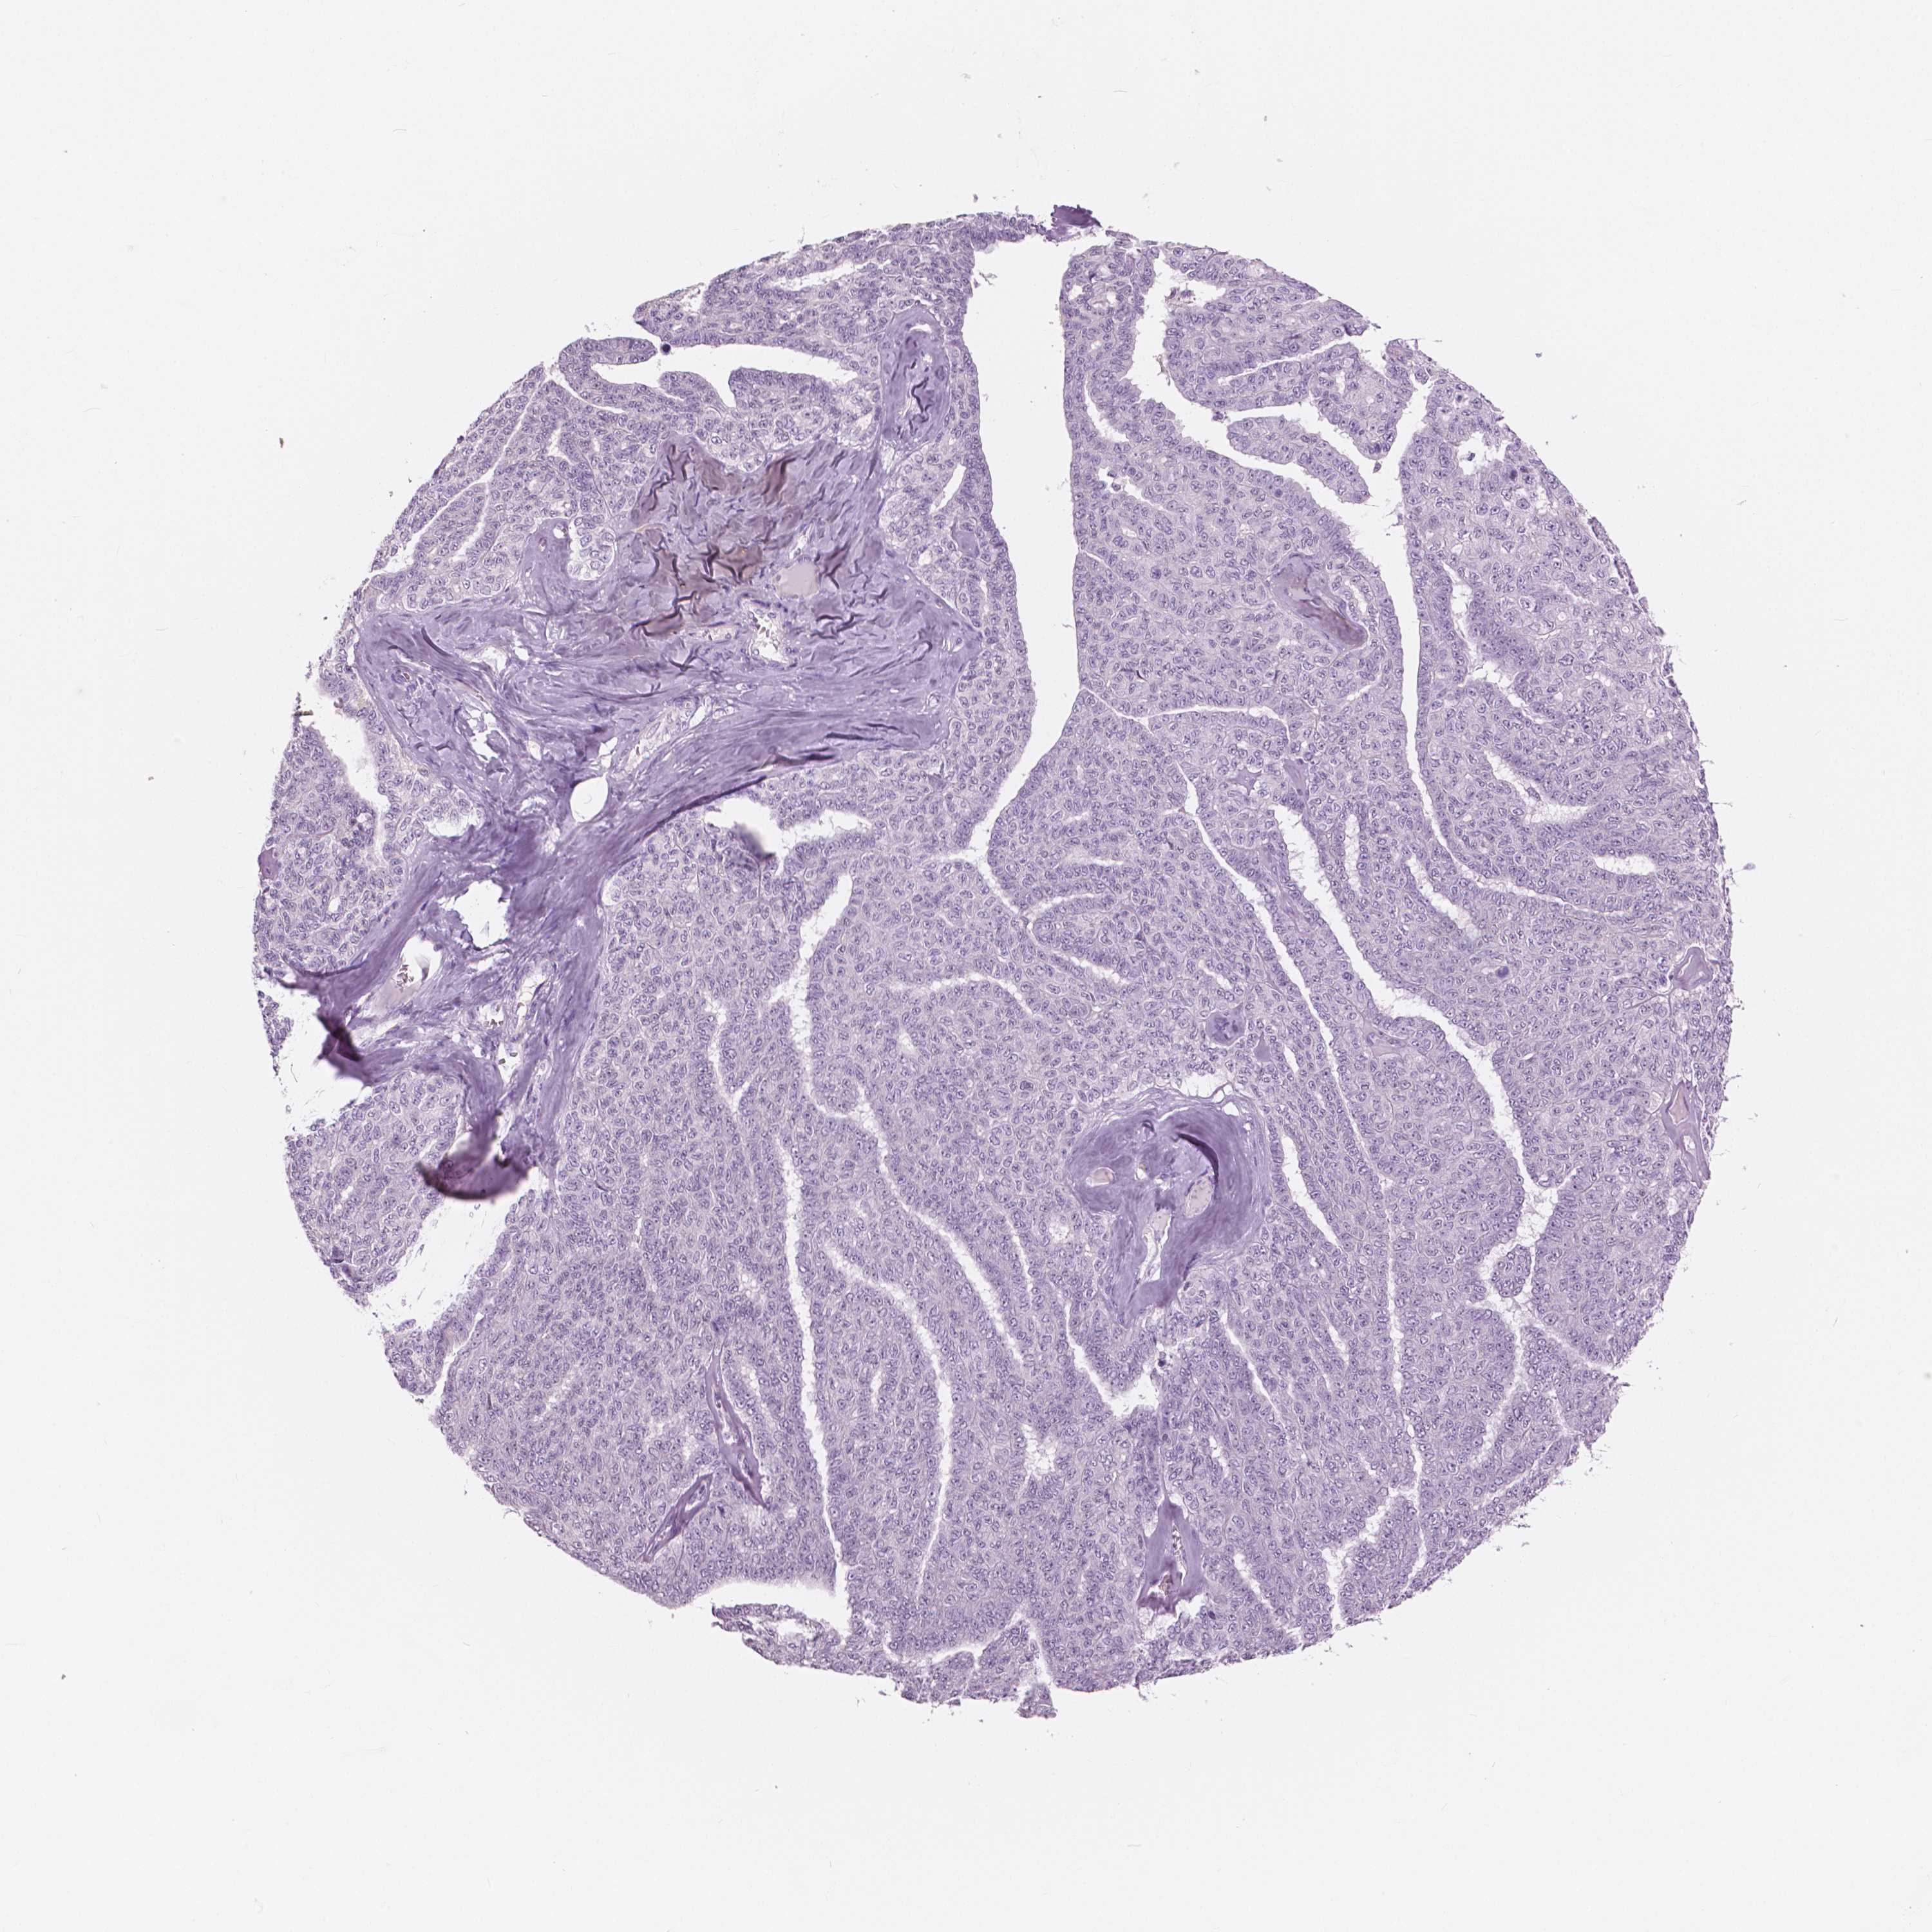

OVARIAN CANCER - Protein expressioni

A mouse-over function shows sample information and annotation data. Click on an image to view it in a full screen mode. Samples can be filtered based on level of antibody staining by selecting one or several of the following categories: high, medium, low and not detected. The assay and annotation is described here.

Note that samples used for immunohistochemistry by the Human Protein Atlas do not correspond to samples in the TCGA dataset.

Antibody stainingi

Antibody staining in the annotated cell types in the current human tissue is reported as not detected, low, medium, or high, based on conventional immunohistochemistry profiling in selected tissues. This score is based on the combination of the staining intensity and fraction of stained cells.

Each image is clickable and will lead to virtual microscopy that enables deeper exploration of all samples and also displays staining intensity scores, fraction scores and subcellular localization as well as patient and tissue information for each sample.

Antibody HPA035472

Antibody HPA035473

Antibody HPA064835

Cystadenocarcinoma, serous, NOS

Cystadenocarcinoma, mucinous, NOS

Carcinoma, endometroid